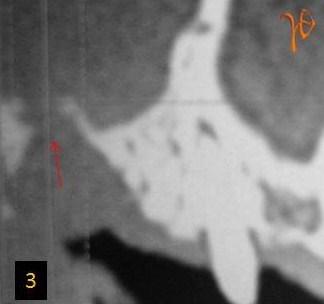

3

Εικ. 3: Στεφανιαία τομή της υπολογιστικής τομογραφίας που αποκαλύπτει την παρουσία στοματοκολπικής επικοινωνίας (βέλος).